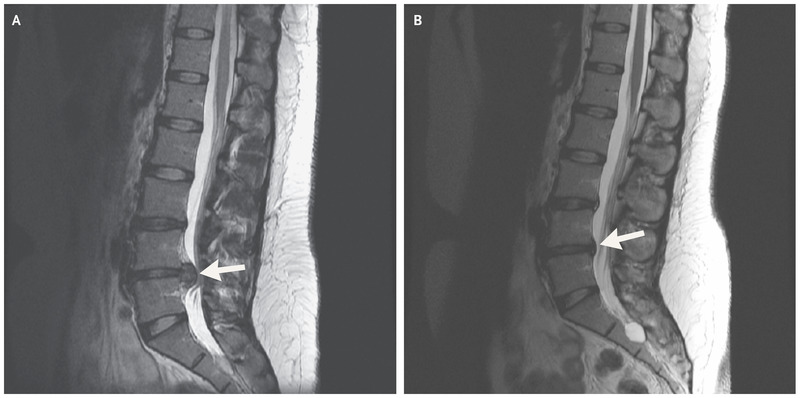

تشخیص دیسک کمر با انجام یکسری معاینات همچنین رادیوگرافی که مهمترین آنها ام آر آی می باشد انجام می شود. به صلاحدید پزشک ممکن است نیاز به عکسهای ساده هم داشته باشید. شایعترین محل دیسک در بین سه مهره پایینی کمر می باشد.